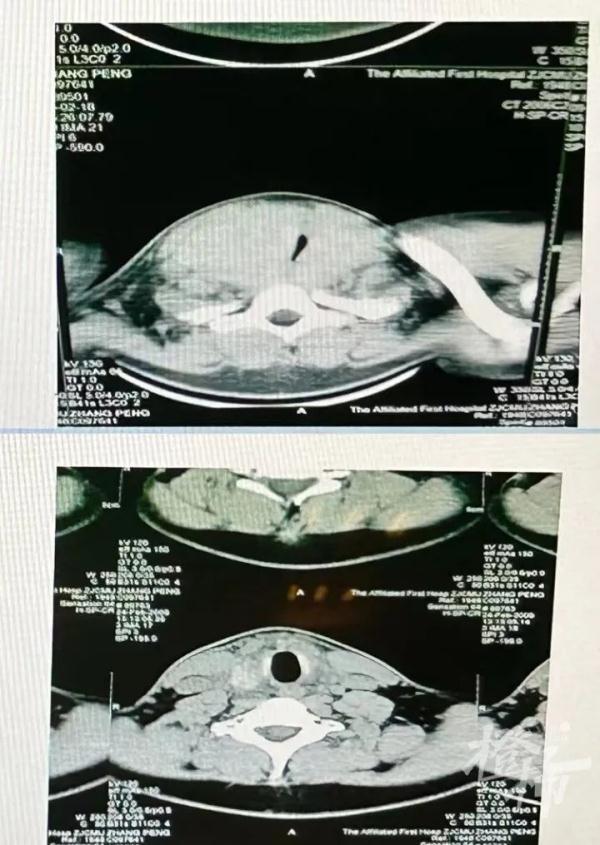

20岁的小雨也有类似的经历,他比小玲的情况更严重,他来医院时吐气都很困难,睡觉时出现了严重的打呼声,甚至影响到了在隔壁睡觉的父母。通过甲状腺B超检查,小雨的气道被甲状腺肿瘤严重压迫。“原本通畅的气道被压迫到只剩一道极窄的缝隙,所以他才会出现吐气困难、打呼严重的情况。”傅教授说。手术后,小雨终于恢复正常,能够顺畅吐气了。

小雨手术前后的气道对比图。(医院供图)